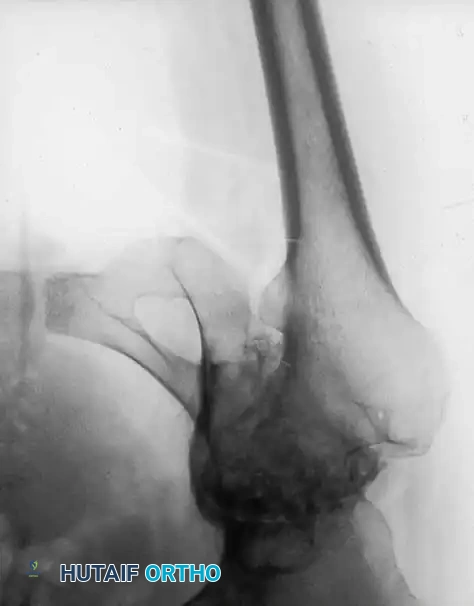

Fig. 7-74 Primary protrusio acetabuli. Otto pelvis in 52-year-old woman. Femoral head has migrated medial to ilioischial (Kohler) line. Hip motion is severely limited.